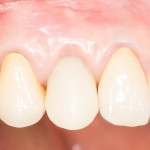

Итак, прошло, примерно, 6 месяцев после имплантации. На имплант клыка установлена постоянная металлокерамическая коронка. Вот она:

Или вот — так любят демонстрировать свои работы врачи-ортопеды:

Есть разница? Сейчас этот зуб выглядит лучше, чем окружающие.

По-моему, очень круто получилось. Давиду респект. Пациентке тоже.

Через 3 месяца- внешний вид искусственного зуба:

Обратите внимание на состояние десны. Проведенные после установки импланта манипуляции позволили не только ее сохранить, но и увеличили объем. Формирование адекватных контуров и объемов слизистой оболочки, особенно в эстетически значимой зоне — еще одно назначение временных коронок на импланты. Все же, формирователи — штука стандартная, в то время как контуры десны как у разных людей, так и у разных зубов, свои — и под каждый зуб десну нужно готовить индивидуально.

Именно поэтому временное протезирование — важный этап всего лечения, который не рекомендуется пропускать. За редким-редким исключением.

Через несколько месяцев Давид меняет временную коронку на постоянную. В данном случае, металлокерамическую. И записывает пациентку ко мне на профосмотр через полгода.